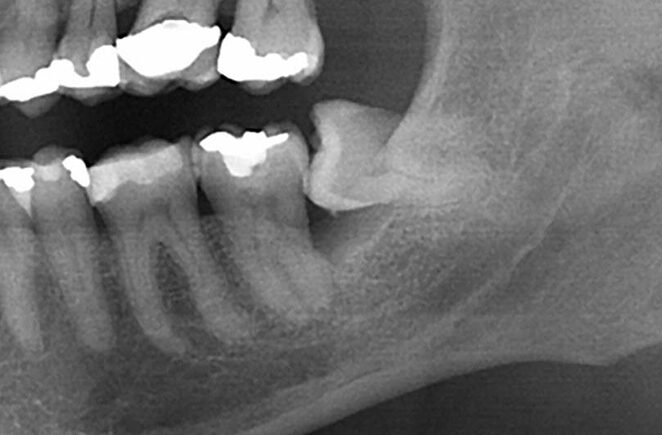

עקירות שיניים – תשובות לשאלות נפוצות

מאת: דר' אוהד שחר עקירות שיניים – תשובות לשאלות נפוצות את המילה "עקירה " שומעים הרבה – מחברים, מקרובי משפחה, ממכרים, מעמיתים לעבודה; ולפעמים זה מגיע גם אלינו. נכון,...